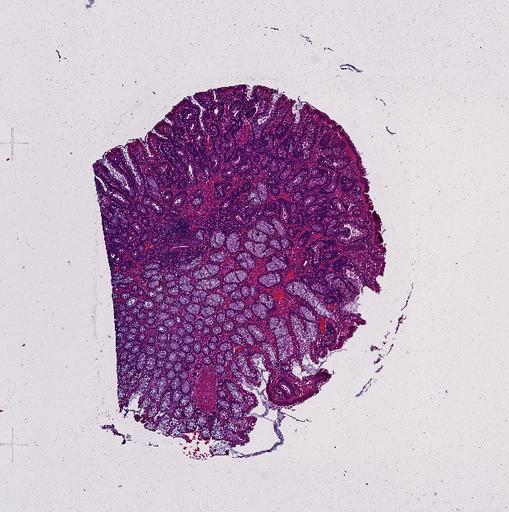

High‑resolution three‑dimensional (3D) tissue atlases promise to redefine how we study cellular architecture‑function relationships in human tissues. Large-scale consortia such as the Human Bimolecular Atlas Program (HuBMAP) systematically build detailed 3D organ maps by profiling serial tissue sections with single-cell spatial technologies. However, an accurate and efficient reconstruction method that can handle atlas-scale datasets remains elusive. We introduce Space-map, an open-source method that integrates single‑cell coordinates with optional histological image features to assemble serial sections into 3D models. Space‑map combines multi‑scale feature matching with large‑deformation diffeomorphic metric mapping, delivering global reconstructions while preserving local micro‑anatomy. To demonstrate the capability of Space-map, we generated a serially sectioned spatial transcriptomics (Xenium, ~2.9M cells) dataset and a spatial proteomics dataset (CODEX, ~2.4M cells). Applying Space-map to these single-cell spatial maps, we built three 3D models for both diseased (colon polyp) and reference colon tissues. These high-resolution 3D models showcase the intricate structure of the human colon across different states. Space-map is fast and highly efficient. We demonstrated its performance and accuracy using in‑house and public datasets. The result shows that Space‑map is 10 times faster and ~2‑fold more accurate than PASTE and STalign, making 3D atlas reconstruction more accessible. Our study provides a new robust and user-friendly software available at https://github.com/a12910/spacemap that can be easily applied for constructing molecular 3D tissue maps of human organs at single-cell resolution.